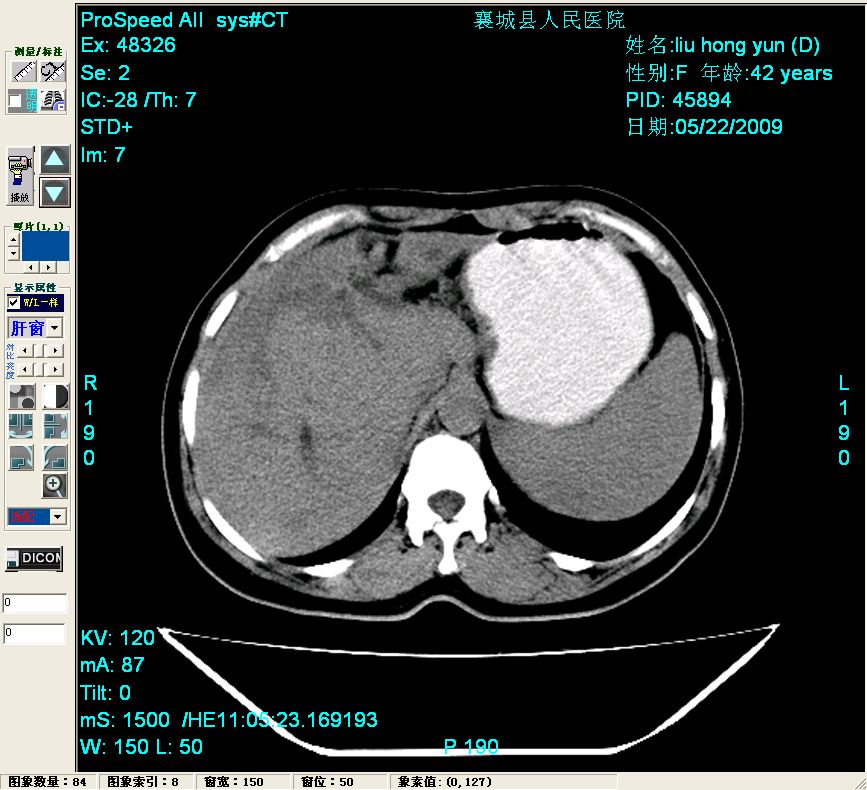

平扫:

平扫左肝外叶体积显著减小,左肝外叶见多房囊性低密度区,左肝实质及右肝前叶浅表实质呈低密度改变,左肝及右肝前叶胆管扩张,脾大